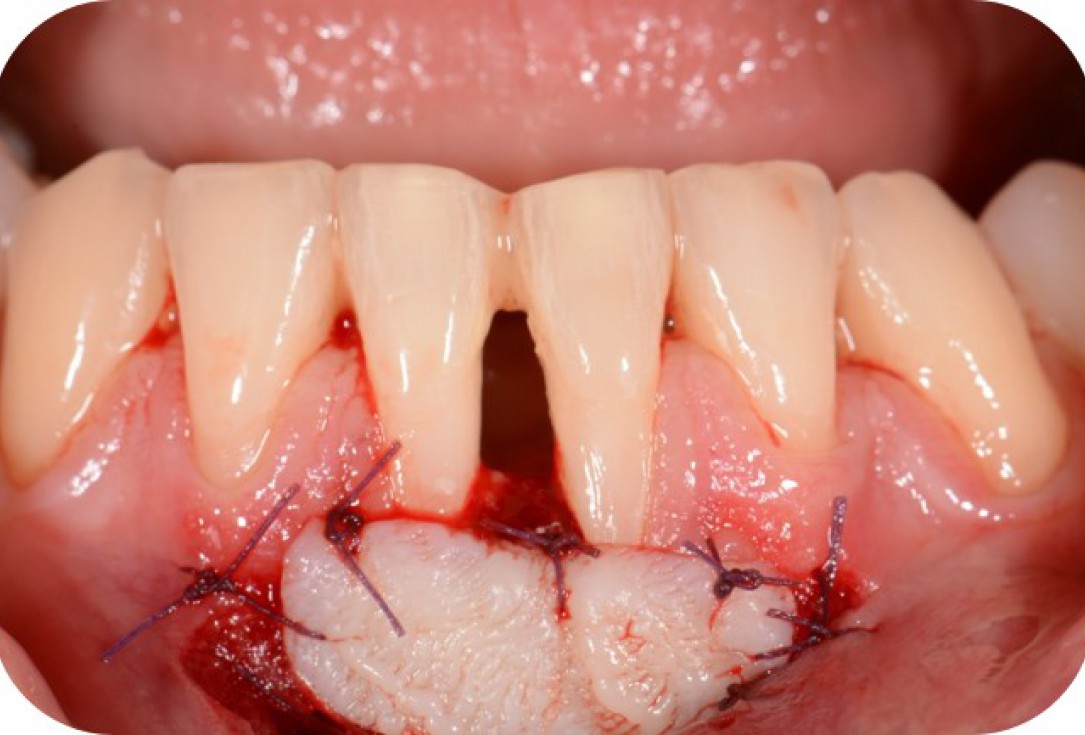

09/12 - Augmentation of keratinized gingiva with a free mucosal graft.Two-wall intrabony defect treated using cerabone® and Straumann® Emdogain® - Dr. D. Rakasevic & Prof. Dr. S. Jankovic